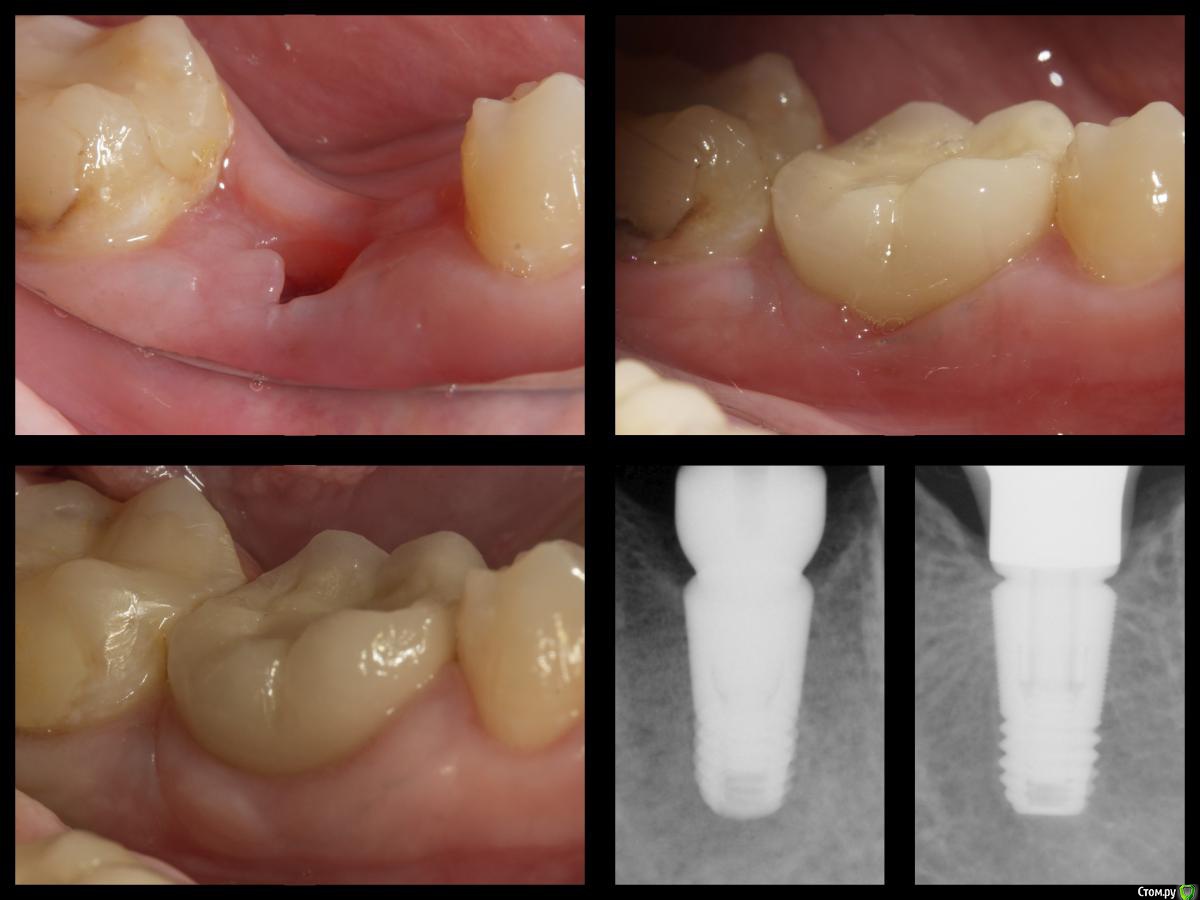

Сегодня опять ругался с ортопедом. Снова сделал уступ 1мм. Не надо так! Стоит формирователь,прекрасная коническая шахта с достаточным объемом закрывающей десны в основании,зачем ее зажимать плоской шляпой? Работа должна садится легко. У платформы десну зажимать нельзя!

Фото по теме не мои, насобирал в фб.

#недозаглубили ....или плюсом десны маловато,вот и при формировании биоширины кость ушла

да нееееет )))) тут как раз наоборот, хирург все норм сделал, а кость ушла от неправильных абатментов.

тот самый случай, когда абатмент с короткой шейкой убил хорошую хирургическую работу